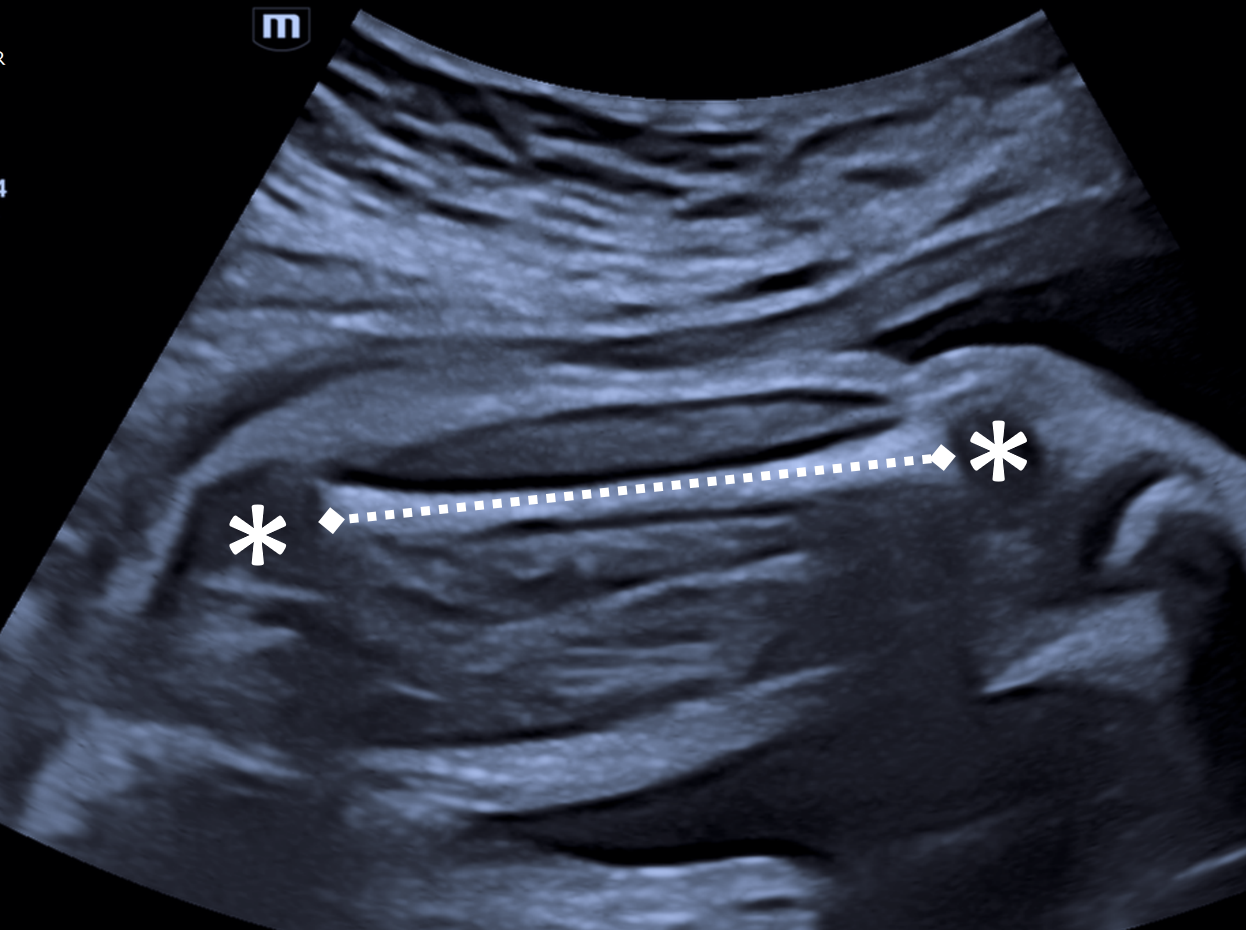

femur_US_biometria

Medida correta do comprimento do fêmur. O fêmur encontra-se aproximadamente horizontal (< 45°), centralizado na tela, com visualização completa da diáfise femoral ossificada, apresentando término abrupto das extremidades (aspecto retangular). A medida corresponde à distância linear entre os limites da diáfise ossificada. Os asteriscos indicam as epífises proximal (cabeça do fêmur) e distal (côndilos femorais), cartilaginosas e hipoecoicas, que não devem ser incluídas na mensuração.